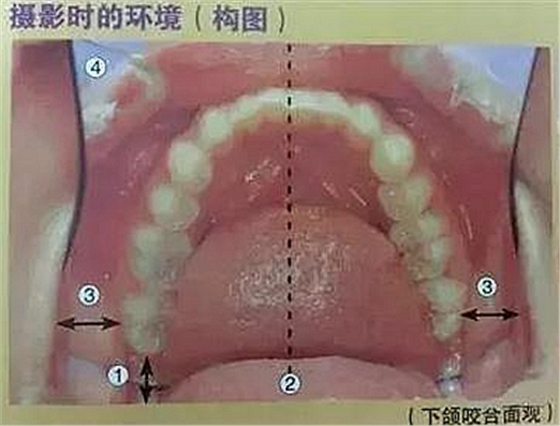

六、咬合面的拍攝

口腔攝影方法與技巧

①反光板離開最后磨牙,不要接觸

②正中線位于反光板中央

③反光板邊緣與左右磨牙的間隙一定

④口角拉鉤打開的幅度大于反光板寬度

⑤反光板開口角度盡可能大(能觀察到前牙區(qū)的舌側(cè))

⑥第一磨牙的咬合平面與焦點吻合

⑦拍攝比例:1:2.4,光圈f22、27,快門速度1/125,閃光強度M/4